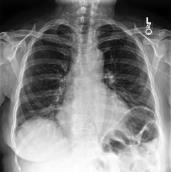

Large numbers of labeled medical images are essential for the accurate detection of anomalies, but manual annotation is labor-intensive and time-consuming. Self-supervised learning (SSL) is a training method to learn data-specific features without manual annotation. Several SSL-based models have been employed in medical image anomaly detection. These SSL methods effectively learn representations in several field-specific images, such as natural and industrial product images. However, owing to the requirement of medical expertise, typical SSL-based models are inefficient in medical image anomaly detection. We present an SSL-based model that enables anatomical structure-based unsupervised anomaly detection (UAD). The model employs the anatomy-aware pasting (AnatPaste) augmentation tool. AnatPaste employs a threshold-based lung segmentation pretext task to create anomalies in normal chest radiographs, which are used for model pretraining. These anomalies are similar to real anomalies and help the model recognize them. We evaluate our model on three opensource chest radiograph datasets. Our model exhibit area under curves (AUC) of 92.1%, 78.7%, and 81.9%, which are the highest among existing UAD models. This is the first SSL model to employ anatomical information as a pretext task. AnatPaste can be applied in various deep learning models and downstream tasks. It can be employed for other modalities by fixing appropriate segmentation. Our code is publicly available at: https://github.com/jun-sato/AnatPaste.